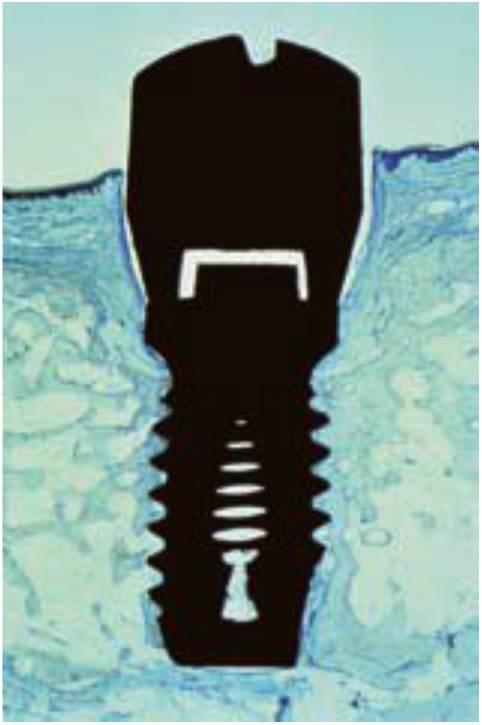

Existen numerosas razones para que un implante fracase en su integración inicial con el hueso. Las causas primarias del fracaso están relacionadas con un excesivo calor durante la preparación de la osteotomía o un exceso de presión en la interfase implante-hueso en el momento de la inserción del implante21 (fig. 4-2). La presión excesiva en la inserción del implante se observa con más frecuencia con los diseños del cuerpo de tipo tornillo cónico. La fuerza de inserción del torque sobre un implante de diseño de cuerpo de tornillo cónico puede aplicar fuerzas excesivas sobre el hueso, lo que conlleva a una reabsorción y fracaso del implante.

Una causa adicional del fracaso quirúrgico son los micromovimientos del implan te mientras se establece la interfase en desarrollo (fig. 4-3). Un brazo fracturado es inmovilizado para evitar movimiento en el foco de fractura para disminuir el riesgo de una falta de unión fibrosa. Se ha observado que movimientos tan pequeños como de 20 micrones pueden causar la formación de una interfase fibrosa en el foco de fractura. Brunski observó el desarrollo de una interfase de tejido fibroso cuando un implante dental se mueve más de 100 micrones durante la cicatrización inicial. El protocolo original Bránemark empleaba un enfoque quirúrgico de dos etapas. Uno de los principales motivos de este concepto era el de colocar el implante en la región de hueso de la cresta o por debajo de ella para disminuir el riesgo de movimiento del implante durante la cicatrización ósea inicial. Schroeder sugirió también un período de cicatrización sin cargas para los implantes, aunque el implante fuera colocado en los tejidos gingivales o ligeramente superior a estos.